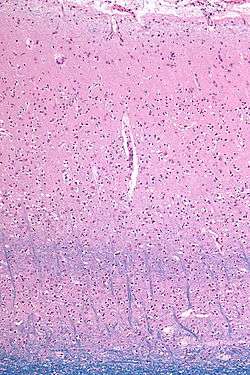

![]() Micrograph showing the visual cortex (predominantly pink). The blue, horizontal band in the lower half of the image are the bands of Baillarger/the line of Gennari. Subcortical white matter (predominantly blue) is seen at the very bottom of the image. HE-LFB stain. | |

The line of Gennari (also called the "band" or "stria" of Gennari) is a band of myelinated axons that run parallel to the surface of the cerebral cortex on the banks of the calcarine fissure in the occipital lobe. This formation is visible to the naked eye and the reason the primate V1 is also referred to as "striate cortex." The structure is named for its discoverer, Francesco Gennari, who first observed it in 1776 as a medical student at the University of Parma.[1] He described it in a book which he published six years later.[2] Although non-primate species have areas that are designated primary visual cortex, some (if not all) lack a stria of Gennari.[3]